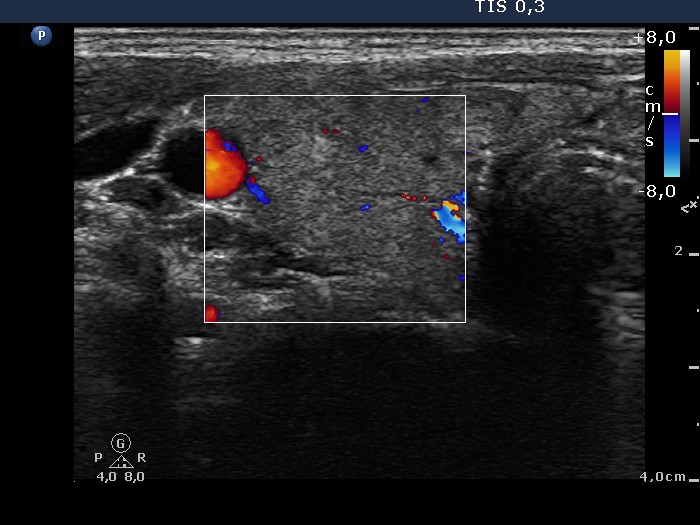

Follow-up investigation 36 months after first visit (ultrasonographic picture 3)

Patient on daily 10 mg methimazole therapy in euthyroid state

Right lobe, transverse scan, color Doppler mode. The vascularization became decreased.